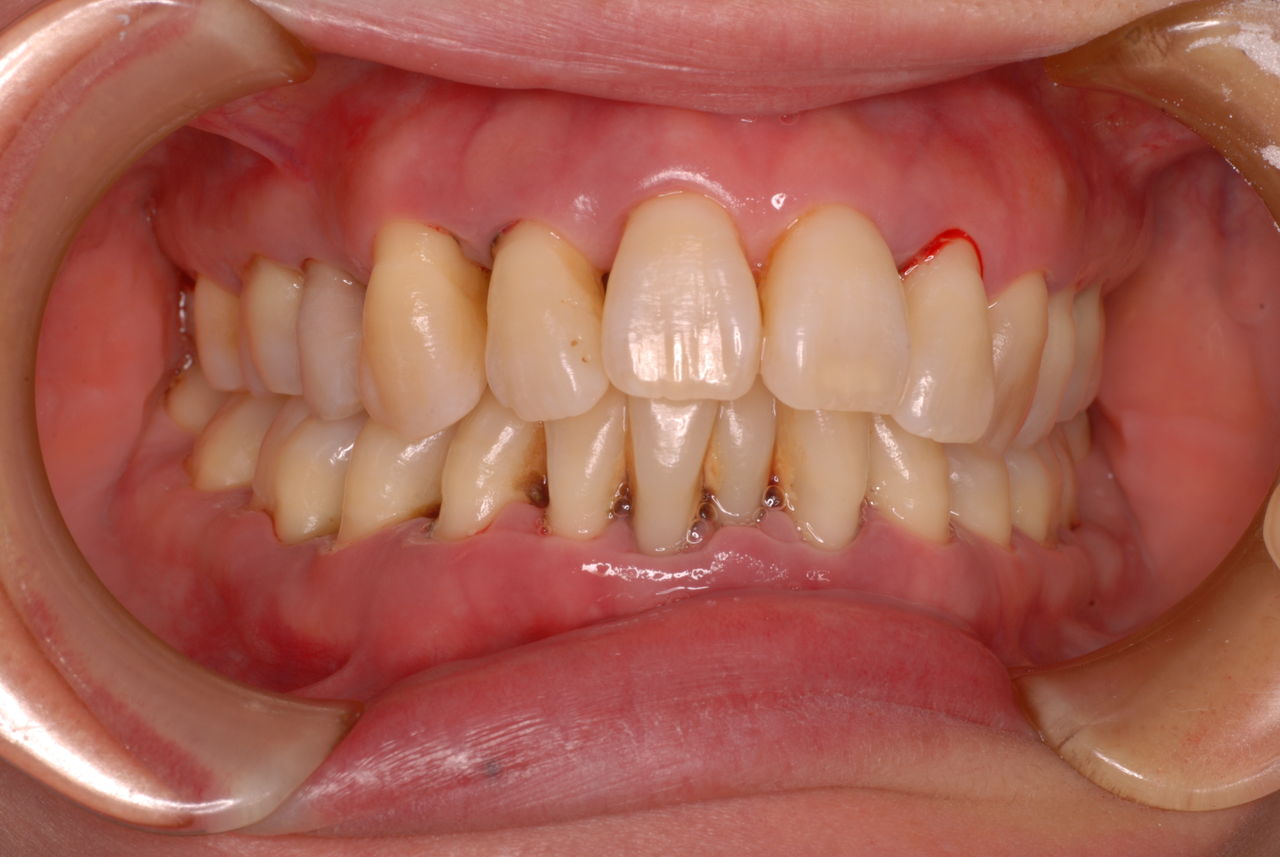

初診から数週間後大分よくなったとはいえまだまだ簡単な検査でも血だらけなのですね。